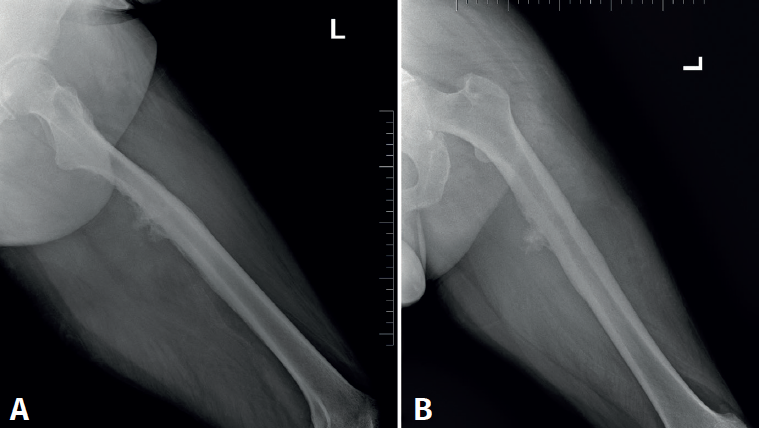

Cincuenta días tras el accidente se realizó fusión lumbar instrumentada L4-L5 con inserción de dispositivo intersomático por vía transforaminal derecha. En el segundo día postoperatorio presentó empeoramiento del dolor, objetivándose en la tomografía computarizada (Figura 2) malposición del tornillo L5 izquierdo que invadía el canal. Se reintervino a los 5 días corrigiendo el trayecto del tornillo. Sin embargo, persistió el dolor. La revaluación del caso, sumada a los hallazgos de EMG, motivó estudios complementarios de pierna y trayecto ciático (Figuras 3 y 4), detectándose una masa tumoral en el fémur izquierdo compatible con sarcoma fusocelular.